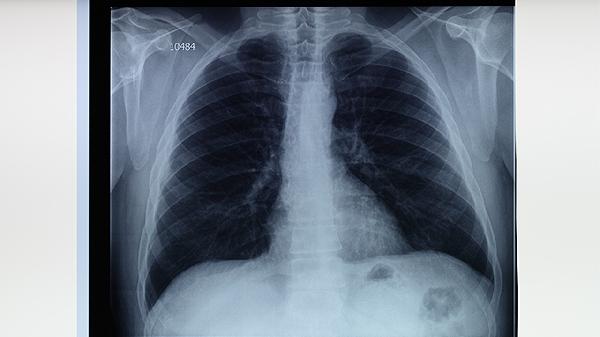

肺结核患者应严格遵医嘱完成6-8个月规范治疗,期间保持清淡饮食,每日摄入足量优质蛋白如鸡蛋、鱼肉帮助组织修复。适当补充维生素B族和维生素C有助于减轻药物副作用,可食用猕猴桃、燕麦等食物。保持规律作息与适度运动,但避免剧烈活动消耗体力。治疗期间若出现皮肤黄染、持续乏力等肝功能异常表现,需立即就医调整用药方案。康复后也需定期复查胸片,确保病灶完全吸收。